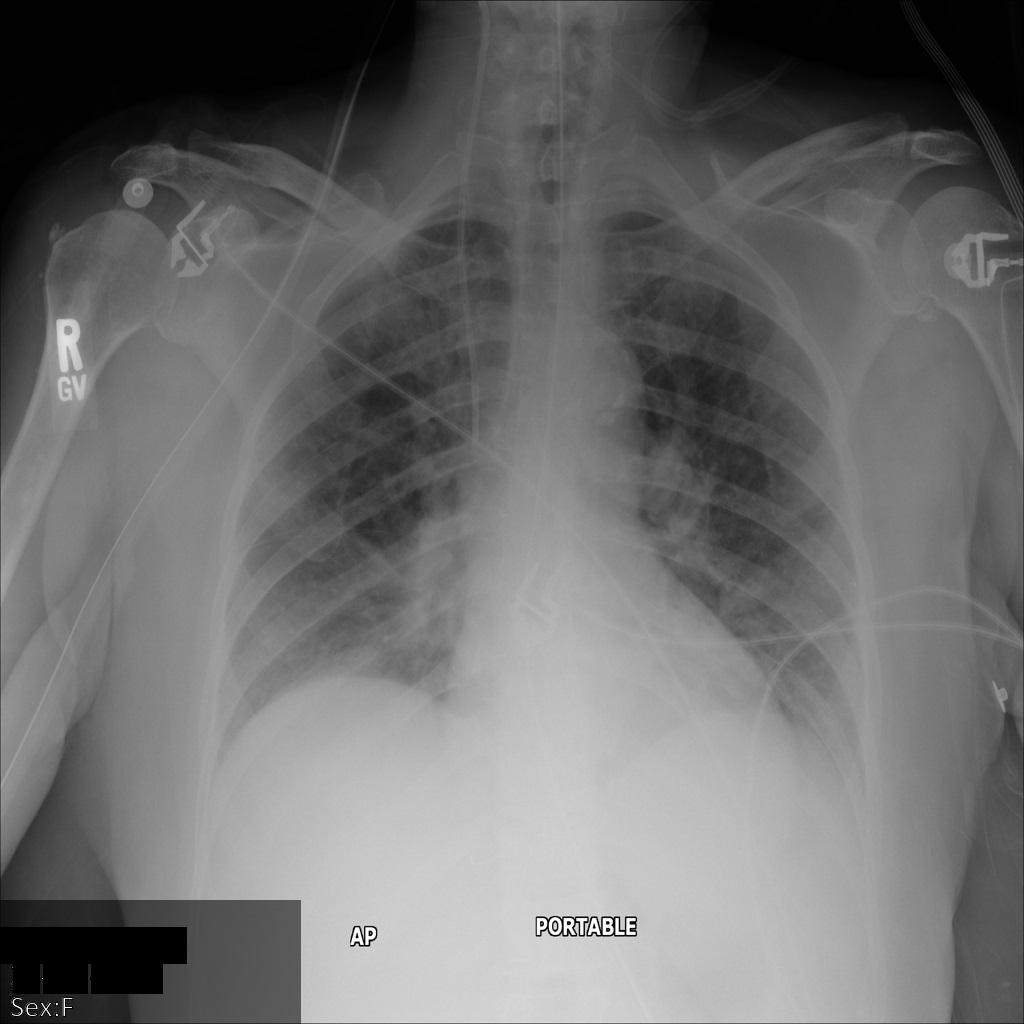

Gambar berikut menunjukkan hasil rontgen pasien yang tidak disamarkan:

Setelah mengirimkan gambar ke Cloud Healthcare API menggunakan opsi REDACT_SENSITIVE_TEXT, gambar akan muncul sebagai berikut:

Anda dapat melihat bahwa hal berikut terjadi:

PERSON_NAMEdi kiri bawah gambar disamarkanDATEdi kiri bawah gambar disamarkan

Jenis kelamin pasien tidak disamarkan karena tidak dianggap sebagai teks sensitif menurut infoType DICOM default.